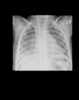

Tuberculous empyema